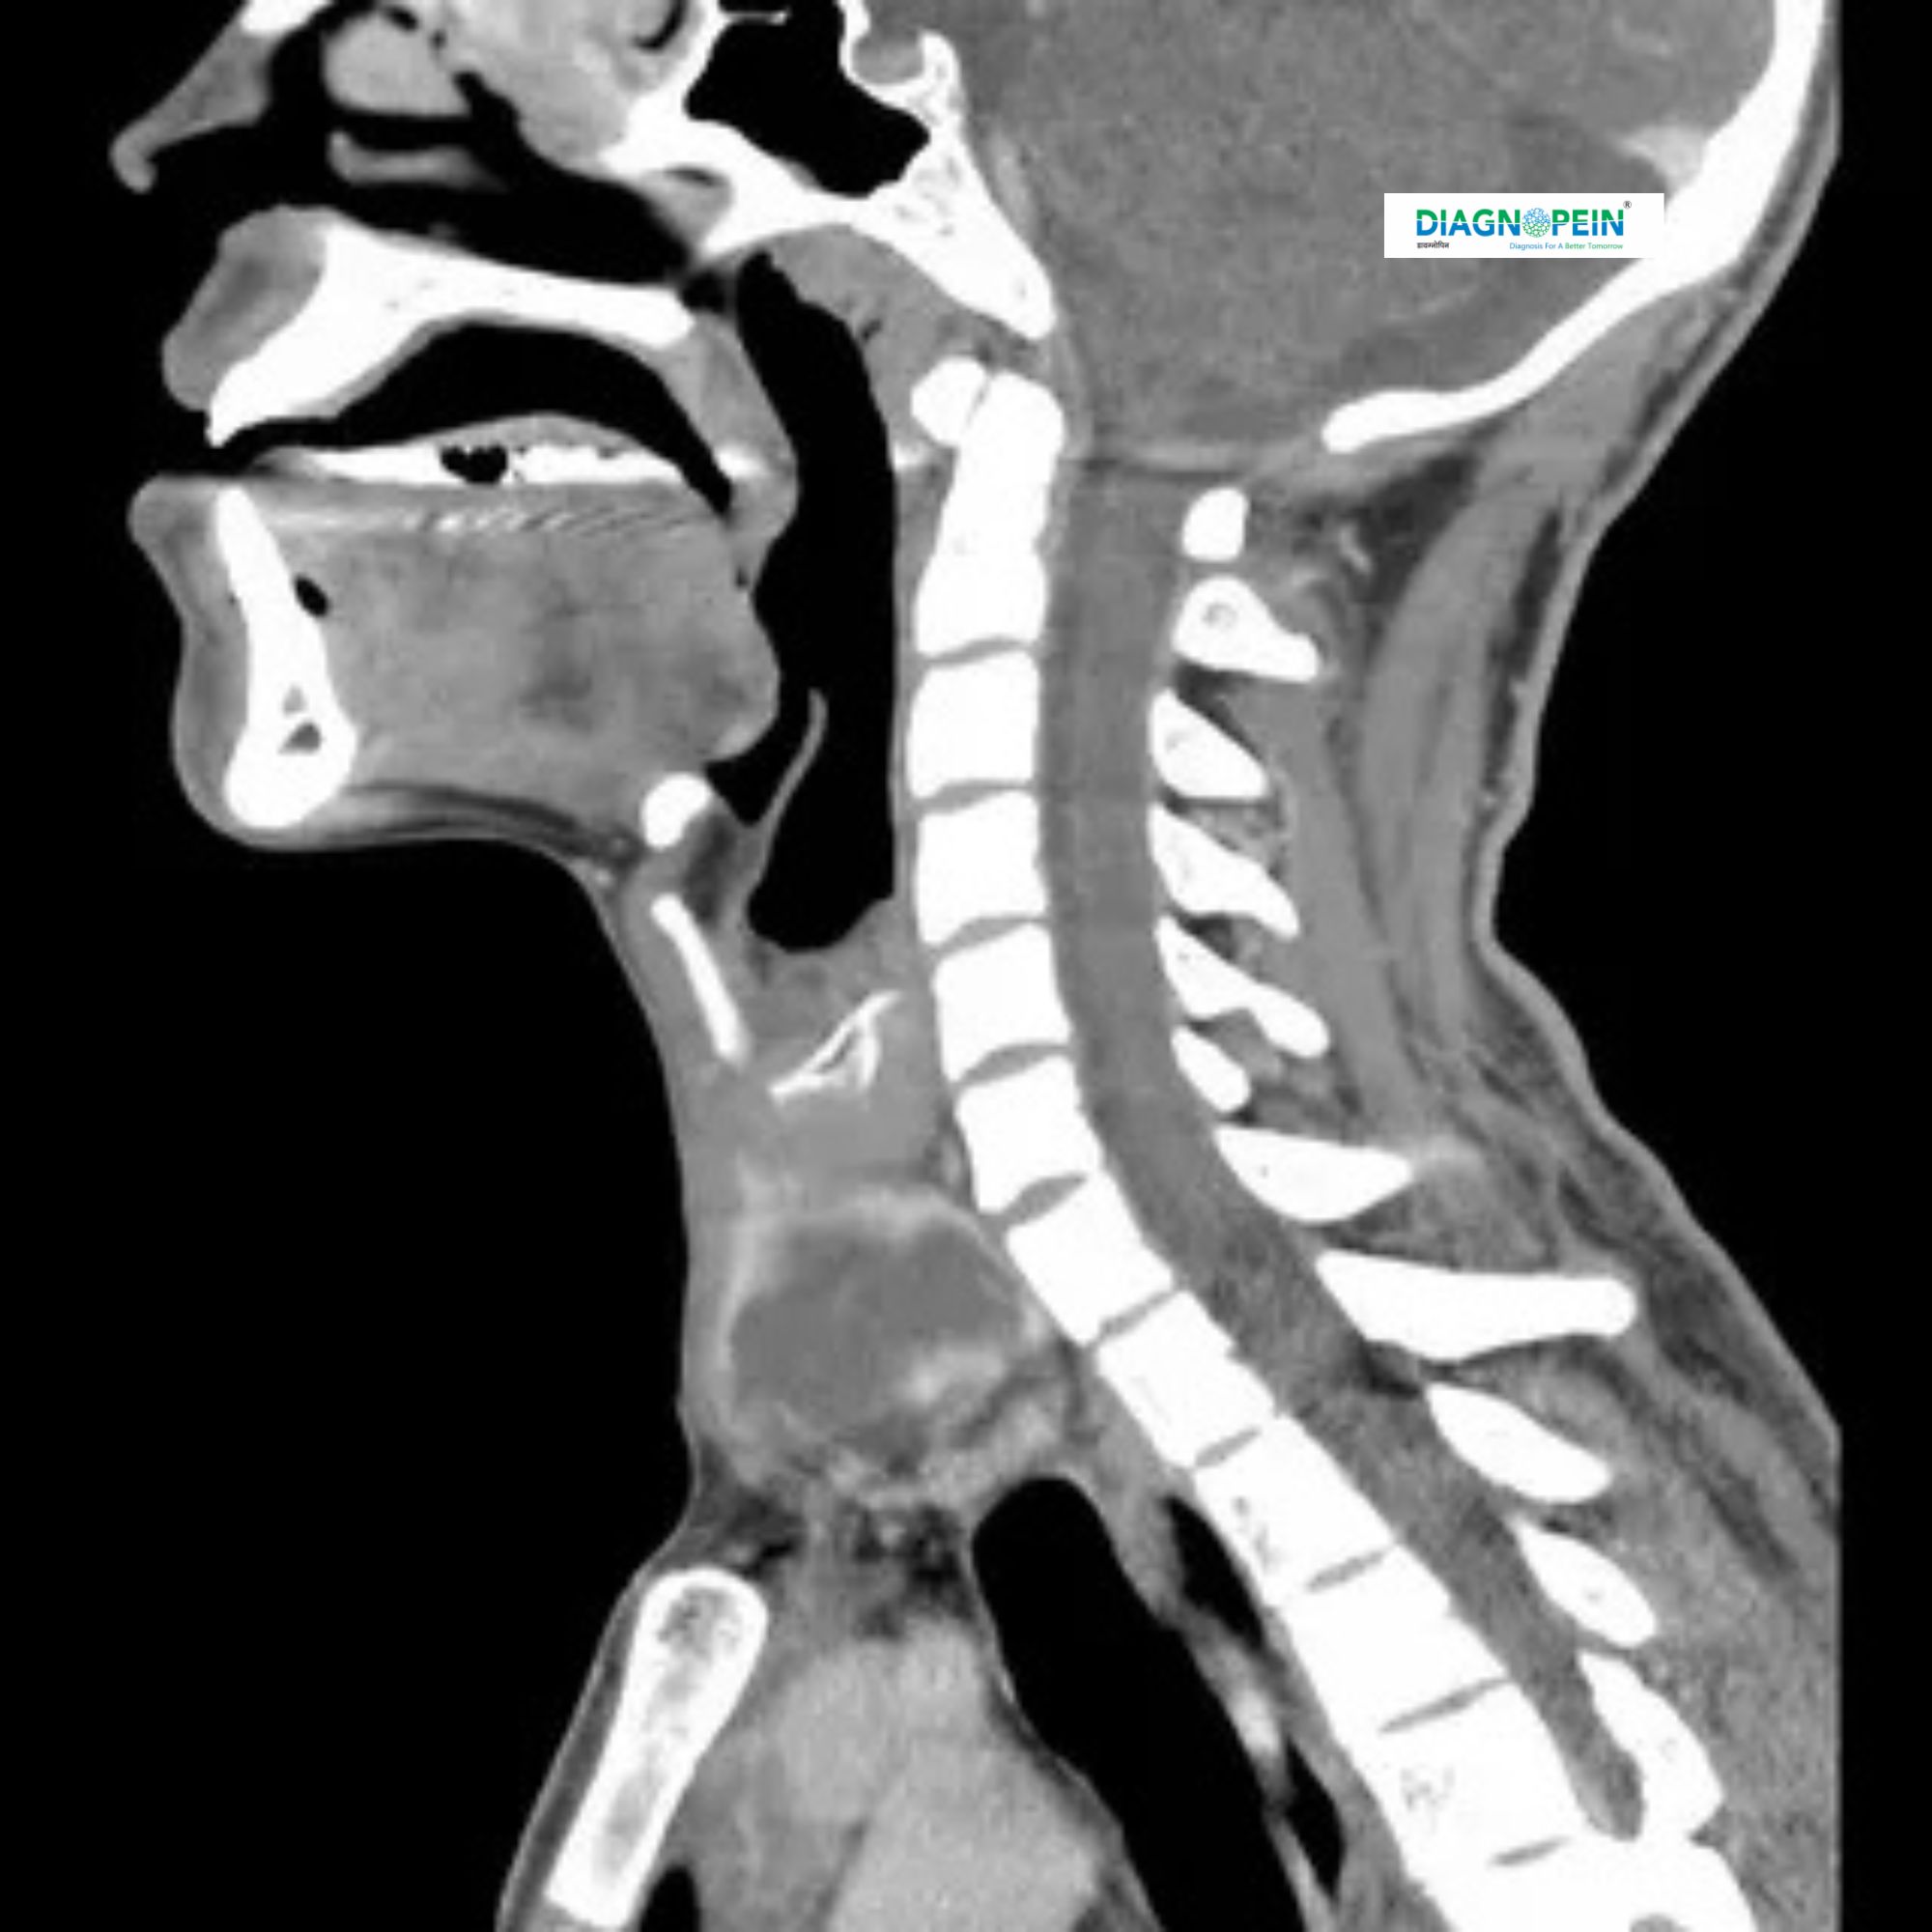

A CT Scan of the Neck – Without Contrast is a specialized imaging test that uses X-rays and advanced computer technology to create detailed, cross-sectional images of the neck region. This scan provides precise visualization of structures like the throat, airway, lymph nodes, salivary glands, thyroid gland, and surrounding soft tissues — all without the use of contrast dye. It is especially useful for patients who are allergic to contrast material or have kidney problems.

A Non-Contrast CT Scan of the Neck offers a clear view of the bones, soft tissues, and blood vessels without the need for any injectable contrast medium. It helps doctors evaluate abnormalities, infections, or injuries while minimizing the risk of allergic reactions.